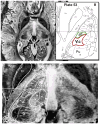

Methods: Using a 7-T MRI scanner combined with an array of acquisition schemes using multiple image contrasts, we obtained high-resolution images of human deep nuclei in healthy subjects.

Results: Superior image resolution and contrast obtained at 7 T in vivo using susceptibility-weighted imaging dramatically improved anatomic delineation of DBS targets and allowed the identification of internal architecture within these targets. A patient-specific, 3-dimensional model of each target area was generated on the basis of the acquired images.